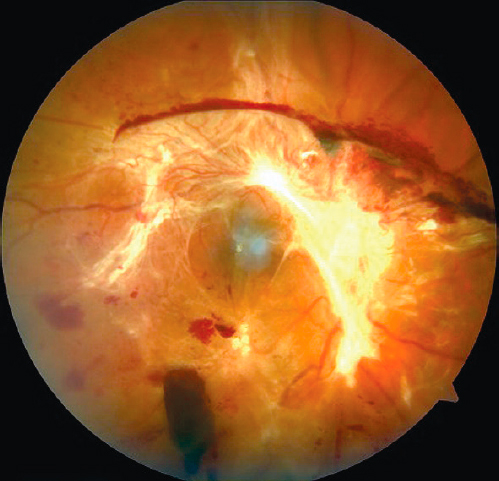

На 31 глазу имелась далекозашедшая стадия ПДР. Она имела выраженную витреоретинальную пролиферацию, на фоне которой в макулярной зоне сформировалась тракционная отслойка сетчатки. В 17 глазах она захватывала фовеальную зону (рис. 2). Тракционная отслойка сетчатки в 10 глазах захватывала один квадрант макулярной зоны, в 5 глазах — 2 квадранта, в одном глазу — 3 квадранта, и в одном глазу всю зону макулы — 4 квадранта (P. Kroll, 1987).

Рис. 2. Пациент Б, 27 лет. Правый глаз до операции. Выраженная фиброваскулярная мембрана, захватывающая диск зрительного нерва, сосудистые аркады. Тракционная отслойка макулы во всех квадрантах. Сахарный диабет 1-го типа в течение 17 лет. HbA1С 10%, нефропатия средней степени.

При удалении плотных преретинальных мембран чаще была возможность избежать повреждения структур сетчатки, хотя в 5 случаях все же не удалось обойтись без ятрогенных разрывов (рис. 4, а). Если же формировался ятрогенный разрыв на прилежащей сетчатке, то мы выполняли ограничительную эндолазеркоагуляцию. Когда разрыв возникал на отслоённой сетчатке, либо когда отслойка сетчатки образовывалась вокруг разрыва, приходилось применять Пфокалин® или газовоздушную тампонаду для мобилизации сетчатки перед ограничительной лазеркоагуляцией. Все операции были завершены силиконовой тампонадой, вязкость 5700 сантистокс [сСт] (рис. 4, b).

Рис. 4. Пациент Г, 38 лет, левый глаз. Сахарный диабет 1-го типа в течение 24 лет, HbA1С 12%: a — интраоперационно — отслойка сетчатки в виде закрытой воронки, выраженная преретинальная мембрана; b — третьи сутки после операции, этап силиконовой тампонады — сетчатка прилежит во всех квадрантах; c — третьи сутки после операции, оптическая когерентная томография — диффузный макулярный отёк.